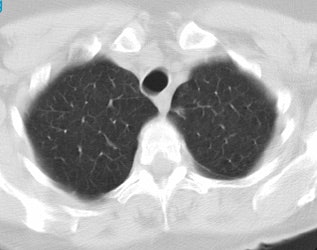

Positive lung cancer screening exam: The patient shown below had undergone lung screening CT in 2002 (left image). The patient was lost to follow-up, but returned for a repeat screening exam in 2007. The 2007 (right image) exam revealed a new stage I NSCLC in the right apex. There is a small linear scar in the medial left apex. |